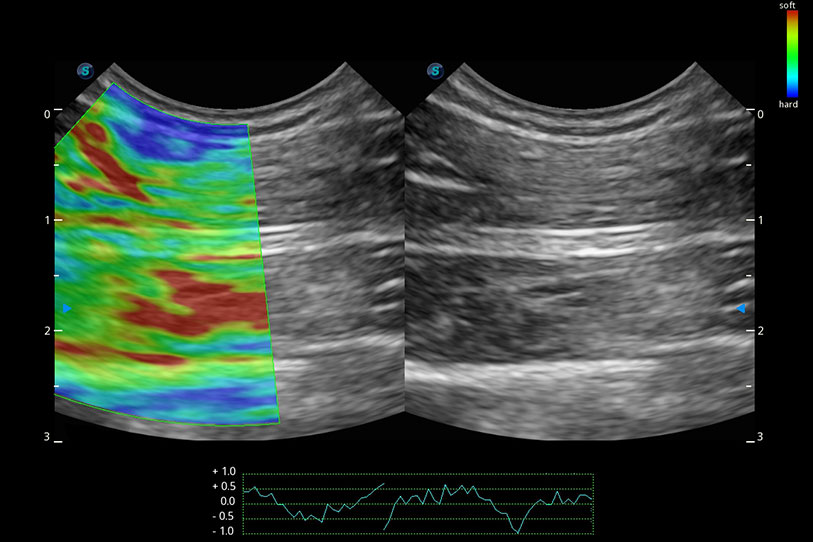

操作简便,无需高频度外力作用即可真实反映组织的形变,快速评估肿瘤良恶性。